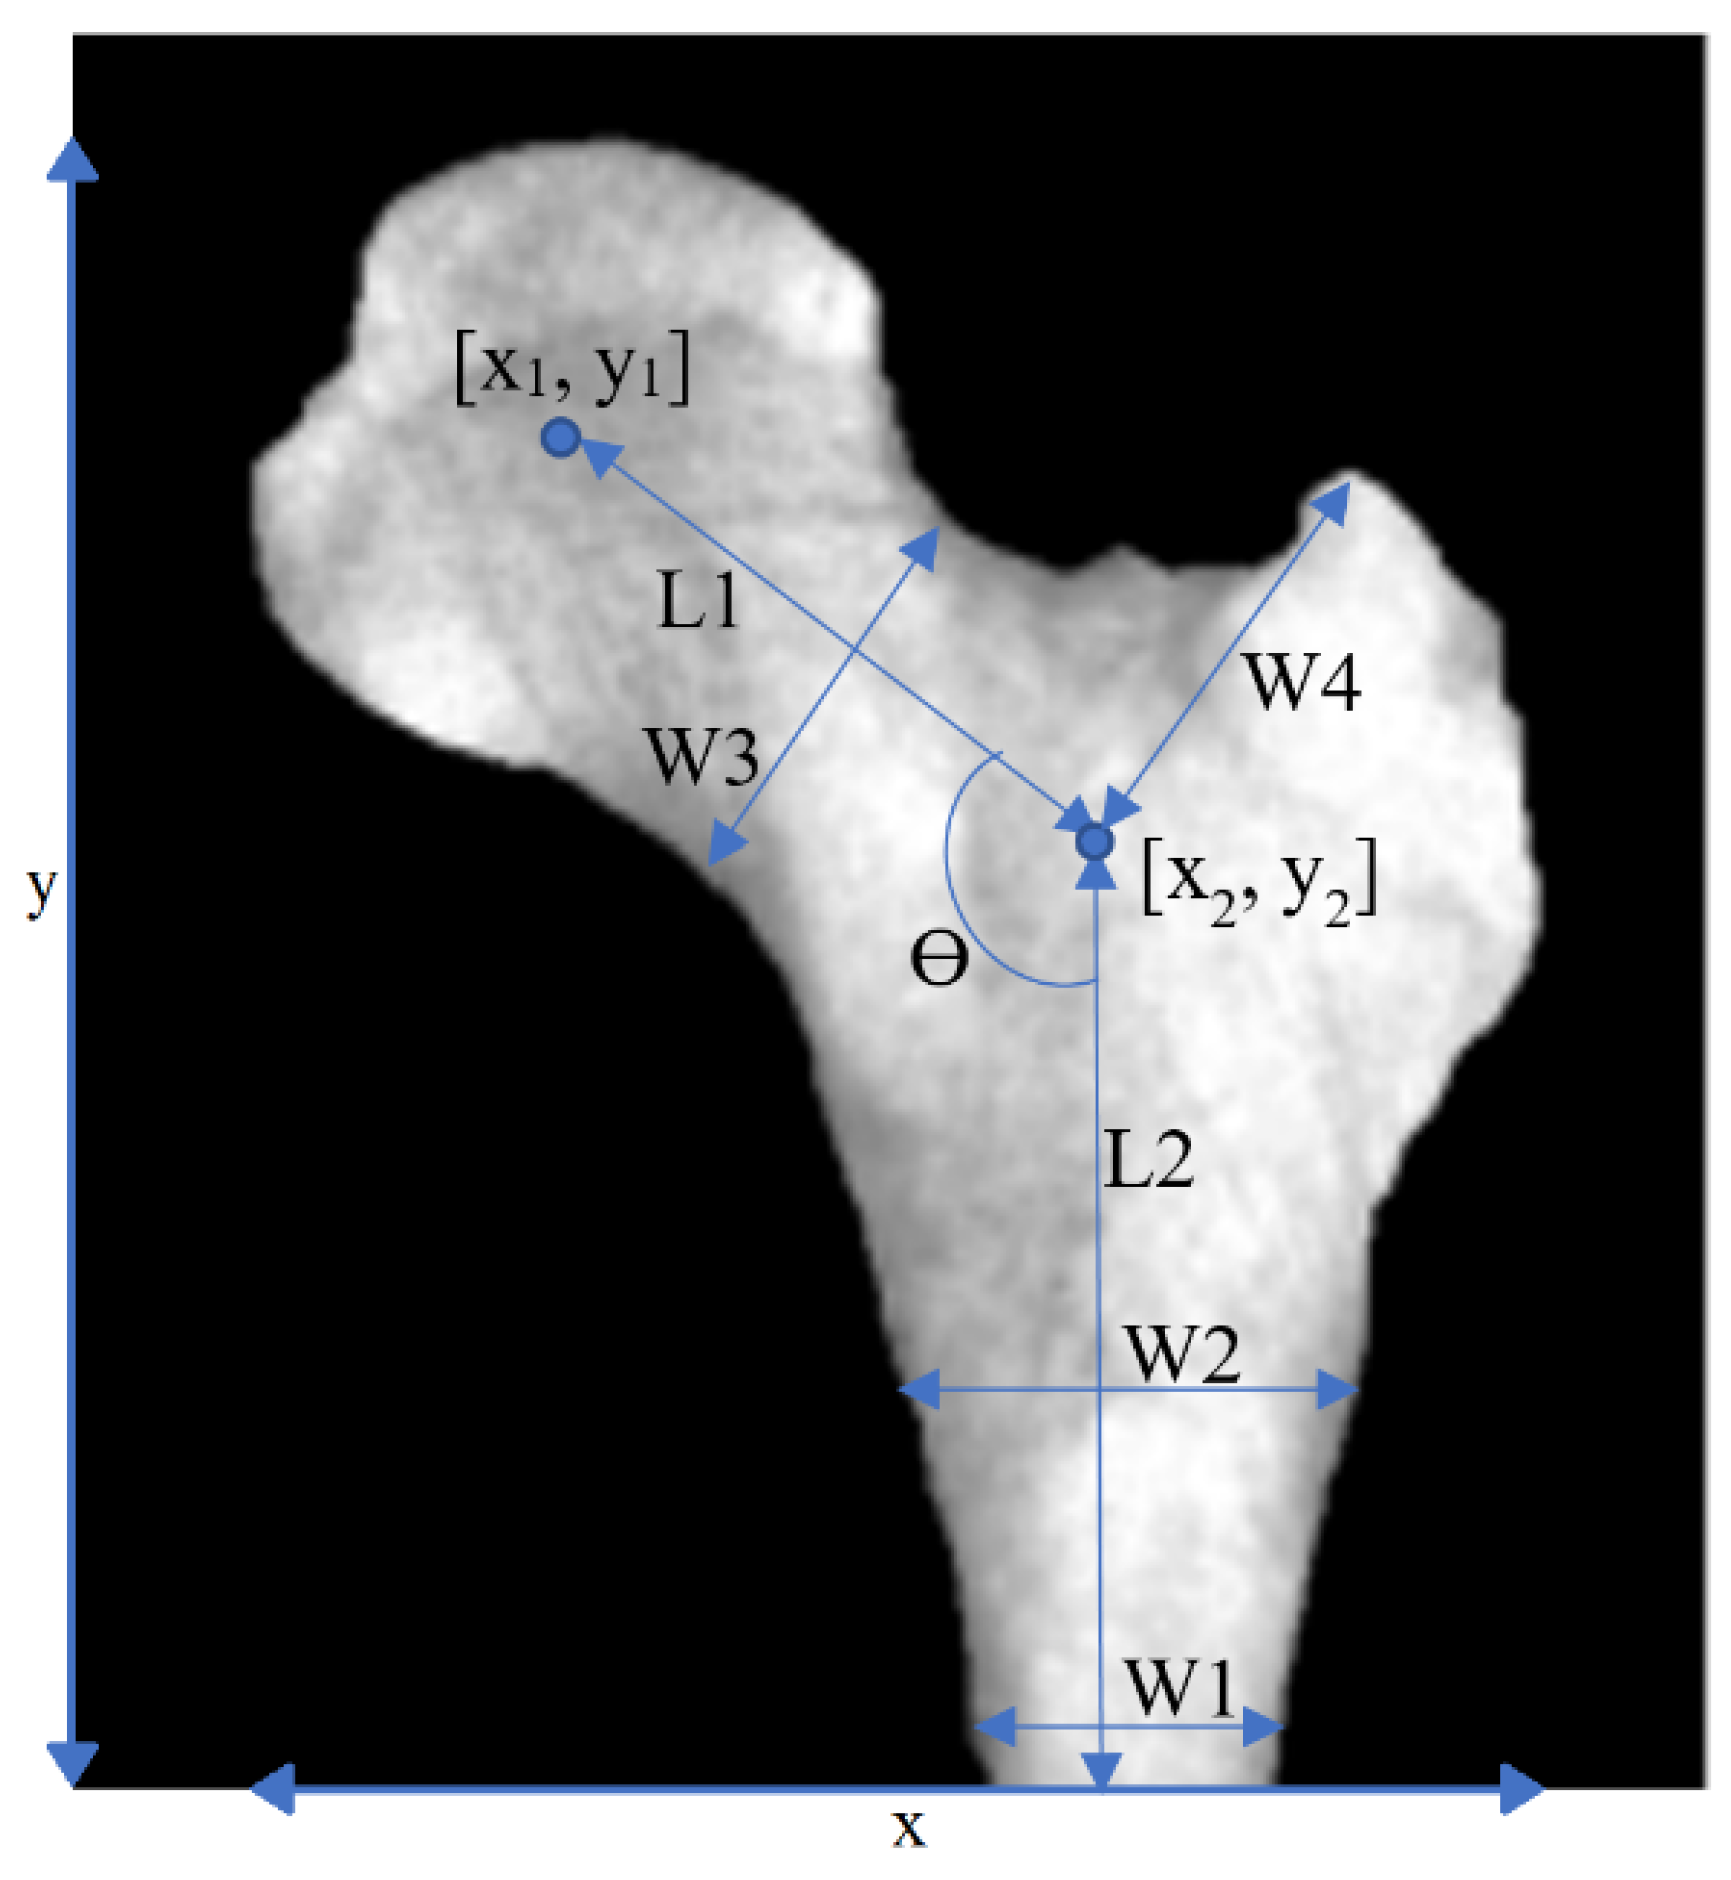

| Geometrical features | As in Figure 2, i.e.,: x1, y1, L1, L2, Ɵ, W0, W1, W2, W3,W4, x, y | 12 |